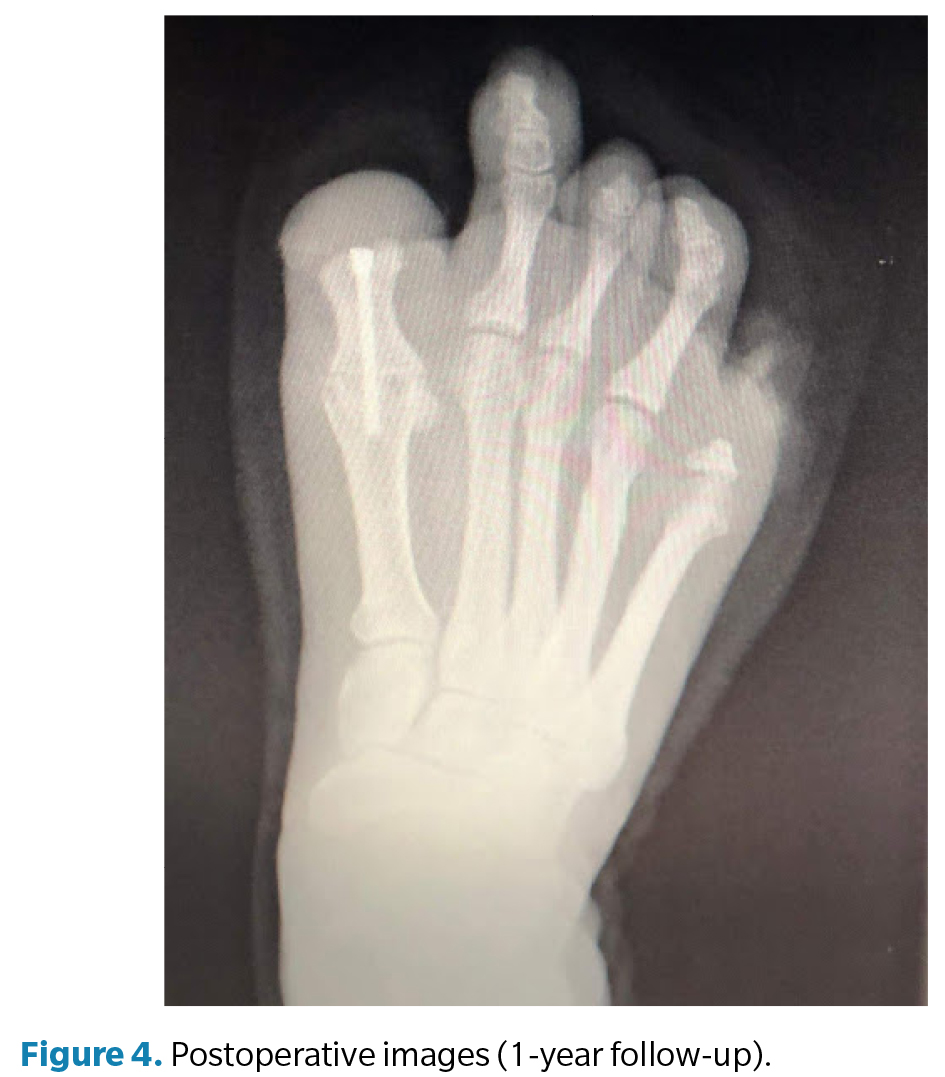

En la exploración clínica (Figura 2) del pie derecho se observó una primera articulación metatarsofalángica rígida, con el hallux en posición de flexión plantar fija y sin falange distal, lo que generaba un muñón doloroso y una alteración de la palanca propulsiva durante la marcha. La deformidad se interpretó como consecuencia de un acortamiento y fibrosis cicatricial postamputación a nivel del flexor residual, sin tracción funcional distal. Se constató dolor por apoyo directo en el pulpejo residual del primer dedo, deformado y con movilidad articular limitada pero presente. El quinto dedo derecho presentaba una cicatriz hipertrófica dolorosa con heloma residual, secundaria a la amputación completa. En el pie izquierdo, la inspección mostró cicatrices normotróficas en los sitios de amputación parcial de los dedos segundo y tercero, sin dolor ni signos de sobrecarga plantar, por lo que no se indicó tratamiento quirúrgico.

La cirugía (Figura 3) se realizó en marzo de 2022 bajo anestesia regional mediante bloqueo poplíteo posterior con sedación consciente supervisada por anestesiólogo. Se administró profilaxis antibiótica con cefazolina 2 g por vía intravenosa 30 min antes de la incisión y se utilizó torniquete neumático a nivel del tobillo, con presión controlada (a 250 mm Hg) y tiempo de isquemia limitado a 45 min. Se efectuó un abordaje dorsal longitudinal sobre la primera articulación metatarsofalángica, respetando las estructuras neurovasculares. Se identificaron los restos óseos irregulares de la falange proximal y se realizó su resección completa, seguida de remodelado de los márgenes óseos hasta obtener superficies regulares y viables. Posteriormente, se prepararon las superficies articulares de la primera metatarsofalángica mediante fresado y curetaje hasta lograr una base sangrante adecuada para la artrodesis. La posición de fusión se determinó intraoperatoriamente mediante pruebas de carga, fijando el hallux en aproximadamente 10° de dorsiflexión respecto al plano del suelo, con el fin de optimizar la propulsión y evitar la sobrecarga plantar en el muñón residual. La fijación definitiva se realizó con 1 tornillo canulado tipo Herbert, verificándose estabilidad intraoperatoria y correcta alineación mediante fluoroscopia (Figura 4). El procedimiento concluyó sin incidencias, con hemostasia cuidadosa y cierre por planos.